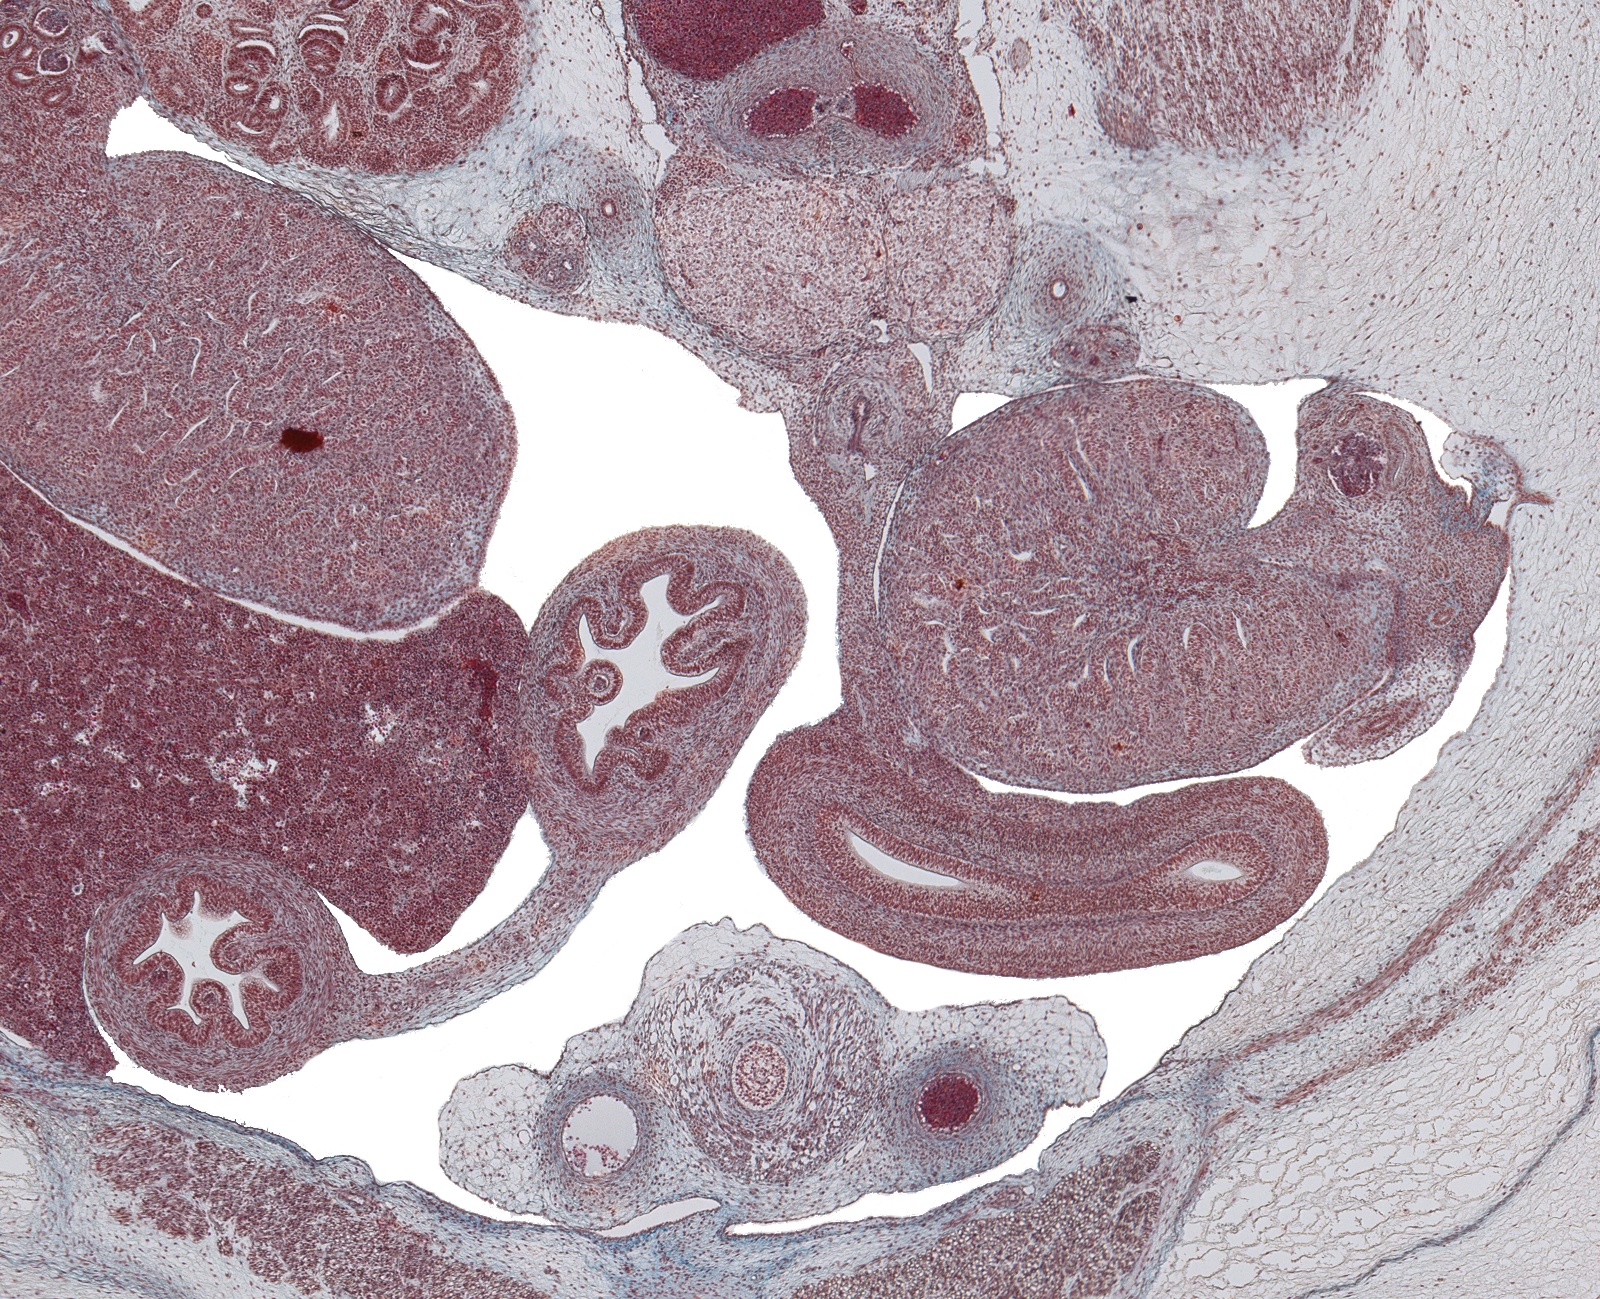

Tissue

Testes, Colon and Upper Bladder

Carnegie Embryo #9226

184-01-01